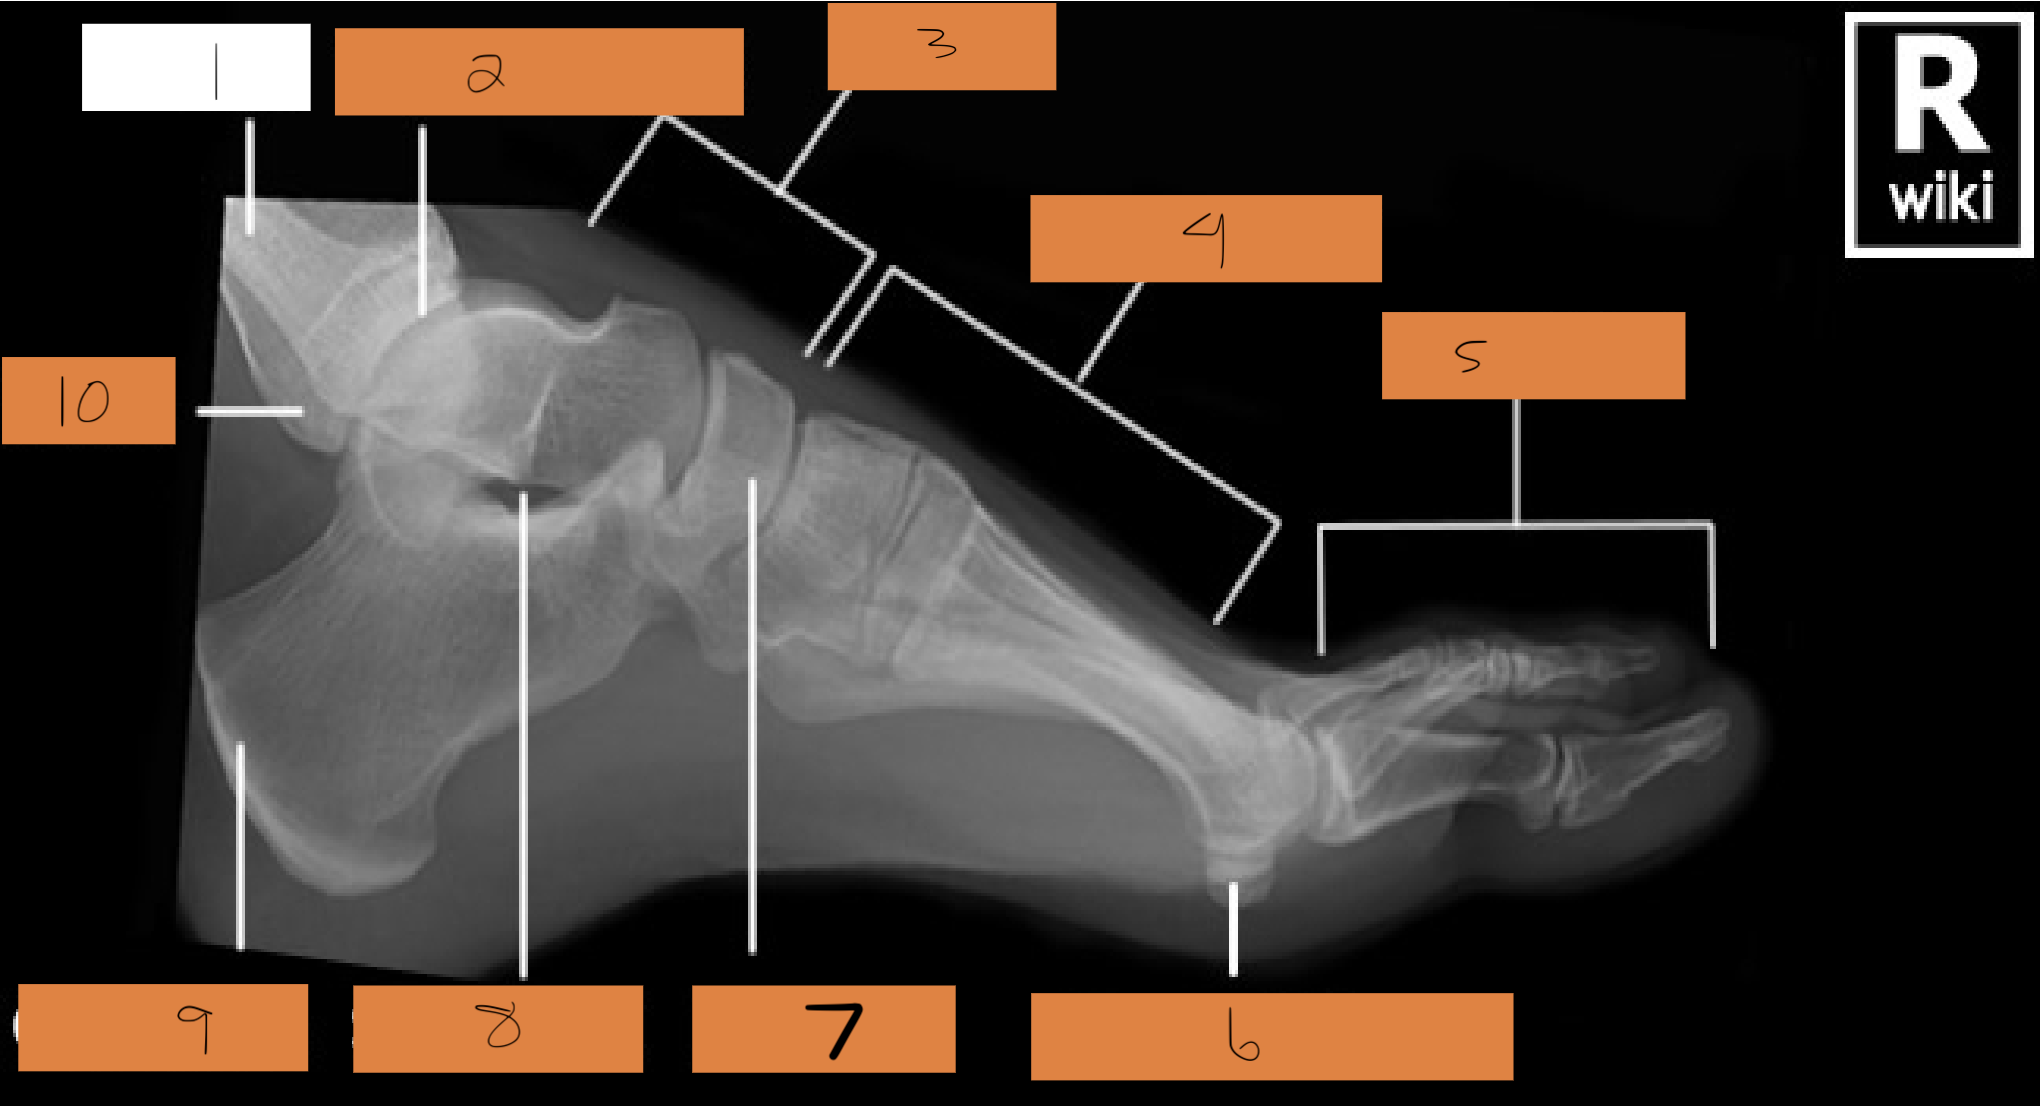

1

tibia

2

tibiotalar joint

3

tarsals

4

metatarsals

5

phalanges

6

sesamoid bones

7

navicular

8

sinus tarsi

9

calcaneum

10

fibula